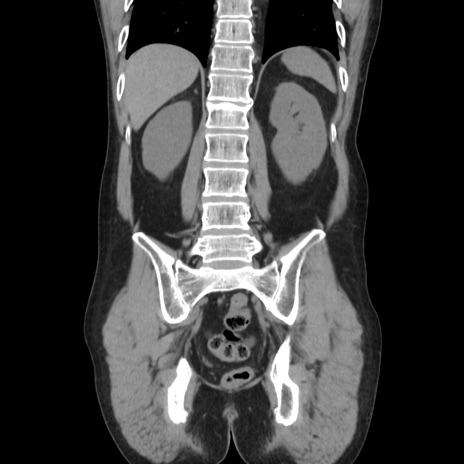

症例37(冠状断像)

【症例】40歳代 男性

【主訴】腹痛

【現病歴】4時間ほど前に電車に乗車中に臍部上より腹痛出現。徐々に増悪し起立困難となり、救急外来受診。生ものは数日食べていない。今朝お雑煮を食べた。

【身体所見】BT 36.8℃、BP 117/84mmHg、HR 91/min、SpO2 97%、苦悶様、腹部:臍上部広範囲圧痛あり、反跳痛±

【データ】WBC 8100、CRP 0.03